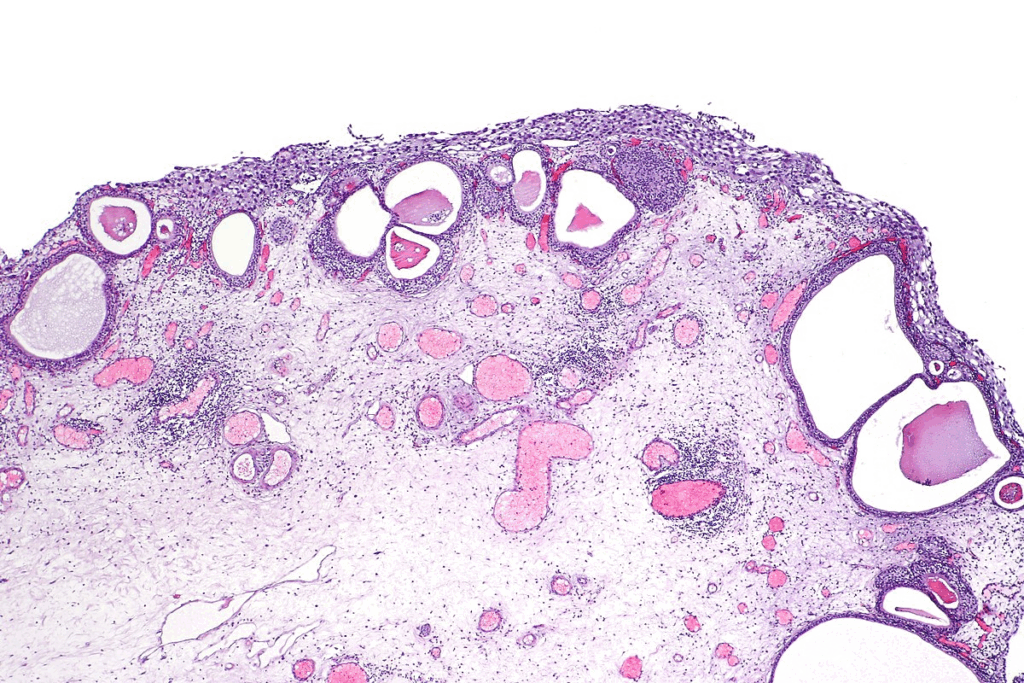

Cellular and Histological Features

CIS has severely dysplastic urothelial cells that haven’t invaded the bladder wall. These cells show nuclear atypia, like big nuclei and irregular shapes. CIS cells are often disorganized and lose normal cell structure.

Nuclear Atypia and Cellular Changes

Nuclear atypia in CIS shows its cancer risk. Cells in CIS have dark nuclei due to more DNA. They also vary in size and shape, showing they are cancerous.

CIS cells also change in cytoplasm, like density and structure. These changes help doctors diagnose CIS and tell it apart from less serious urothelial lesions.